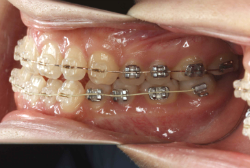

「前歯が重ならない」という主訴で来院したケースです。診断の結果、「重症の開咬」と判明しました。

この方の場合は、マルチブラケット装置は、歯の位置づけを3次元的に正確に行うことの出来る最善の矯正方法です。したがって開咬の治療も、形の改善としては問題なく行うことが出来ます。しかし、開咬が他の症状と少し違う点は、舌や唇の動かし方に問題があることから生じた症状なので、この問題を放置したまま形だけを作っても、時間が経つと簡単に後戻りしてしまうという問題です。つまり、マルチブラケット法で形態の矯正をするのと同時に、原因となっている筋肉の動きを正常に修正しなければなりません。この筋肉の動きを正常に修正する治療が、"筋機能訓練療法(Myo-functional therapy:略してMFT)"といわれるものです。

筋機能訓練療法は、筋機能訓練療法士という特別なトレーニングを積んだ歯科衛生士が行います。内容的には、いろいろなメニューがあり、簡単なものから始めて少しずつ筋肉の力を強めていき最終的には、無意識に起きる舌の突出をなくし、正しい摂食嚥下運動を獲得するまでトレーニングしていきます。この症例は、もちろん筋機能訓練にもしっかり取り組みました。治療後は開咬が改善しただけでなく、出っ歯の症状もなくなり唇の審美性が大幅に改善しました。もちろん奥歯の噛み合わせも正しい状態が確立しています。

開咬の治療の特徴として、上下の歯に自分でゴムを掛ける治療(顎間ゴム)をすることがありますが、この時に「顎関節で音が鳴る、顎が痛い、口が開けにくい」と言った顎関節症状が出ることがありますので、この場合は我慢をせずに担当医にすぐに相談し指示を仰いで下さい。